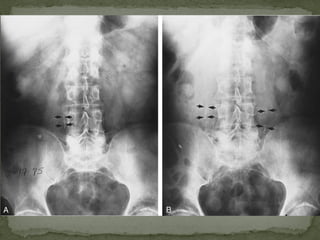

Abdominal radiography : Calcified

vessel wall of AAA (which looks like

eggshell)

 Abdominal radiography :Calcified vessel wall of AAA (which looks like eggshell)  Ultrasound  CT  MRI  Angiography